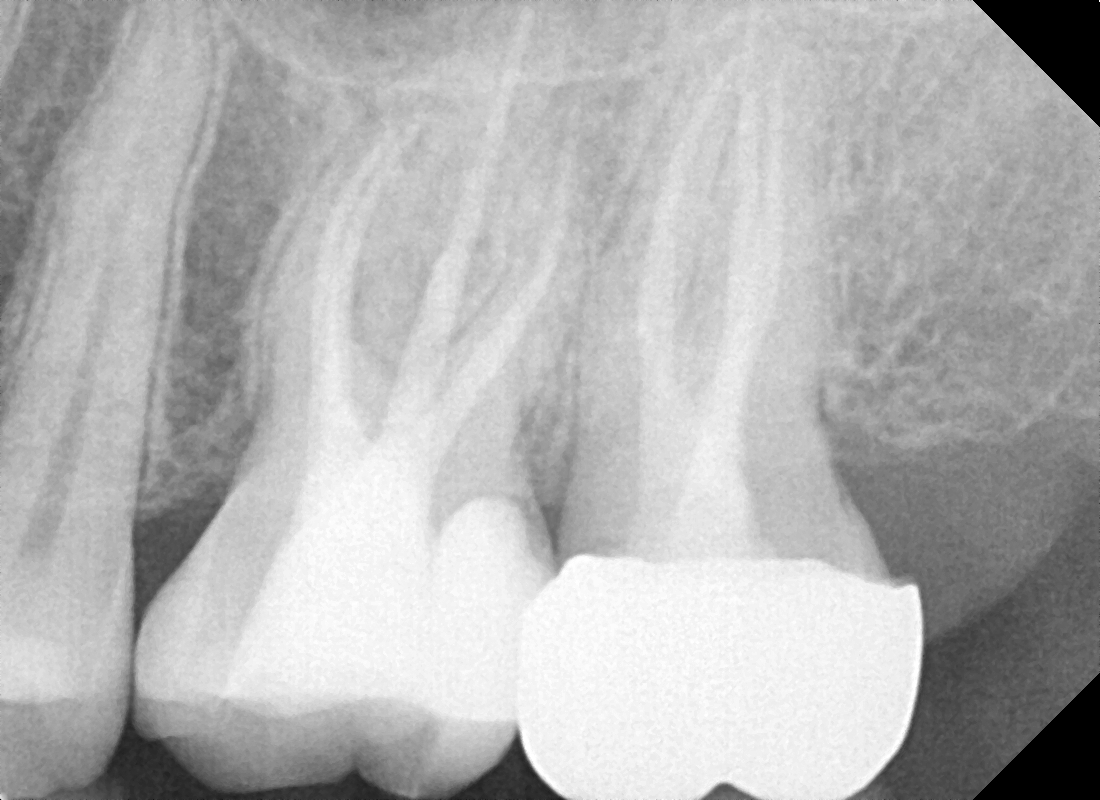

Root canal treatment is a vital procedure designed to save a severely infected or damaged tooth instead of extracting it. When the pulp inside your tooth (containing nerves and blood vessels) becomes inflamed or infected, it can cause severe pain and discomfort. During a root canal, the infected pulp is carefully removed, the inside of the tooth is cleaned and disinfected, and then filled and sealed. This precise root canal procedure allows you to retain your natural tooth, preventing further complications. At True Dental Co, we focus on precise, pain-free root canal treatment to ensure your comfort and preserve your tooth.